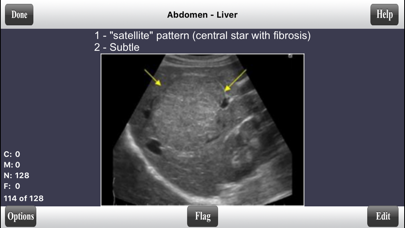

Liver - 128 flashcards